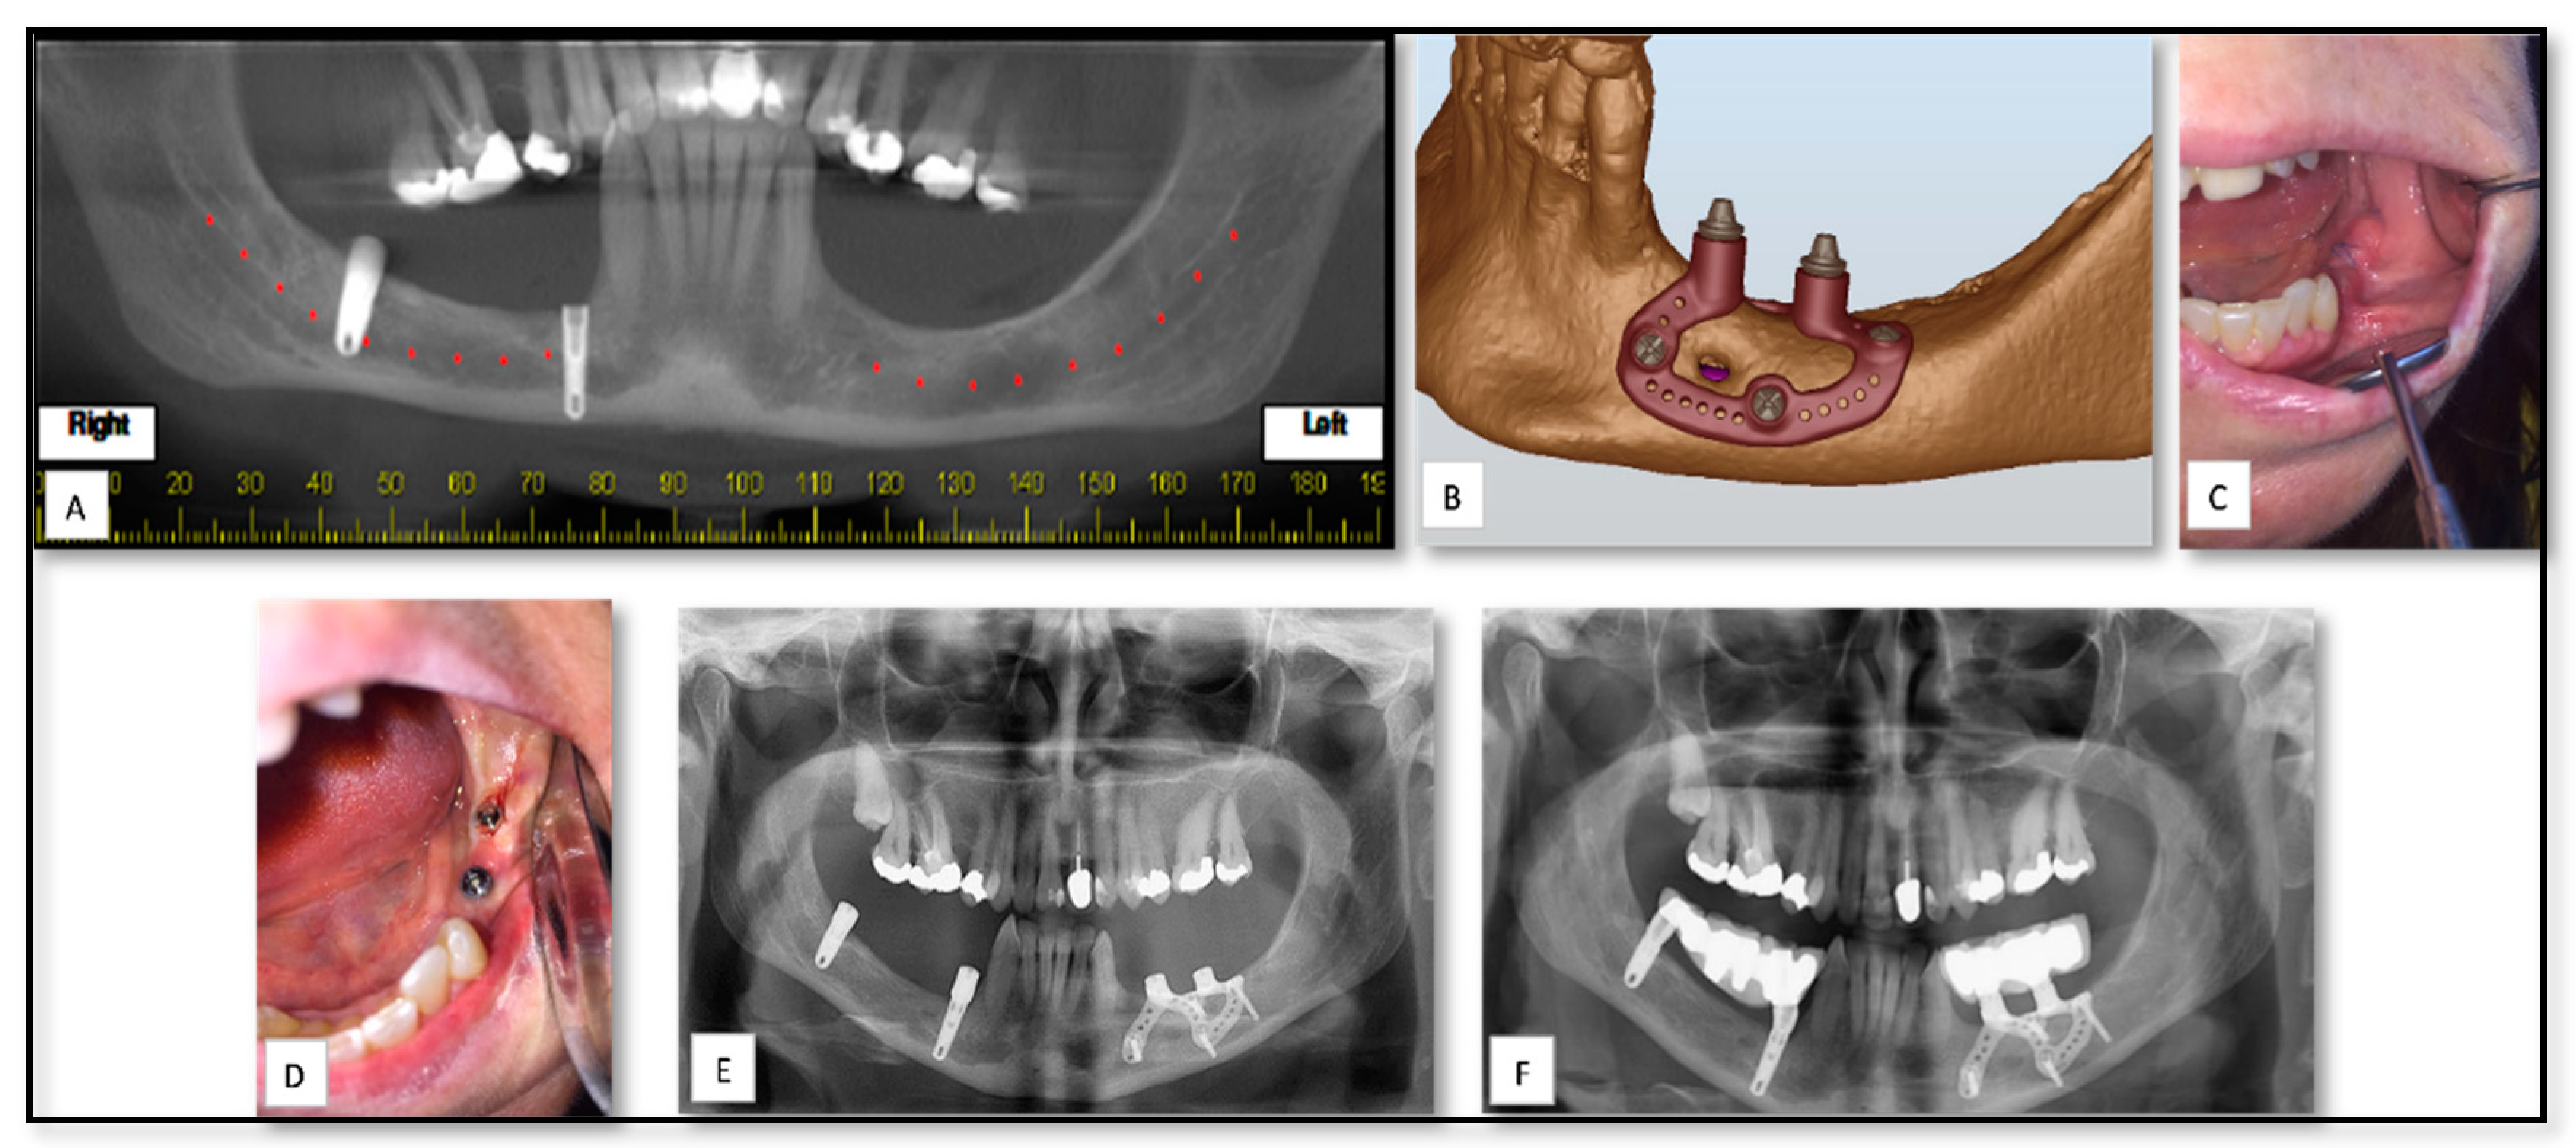

5.2. AM for of Pre-Prosthetics Patient-Specific Implant (PSI) Manufacturing

| 12 | 44 | F | Pre-prosthetics | Mandible | PSI of sub-periostal dental implant | Titanium | − | Mild edema |